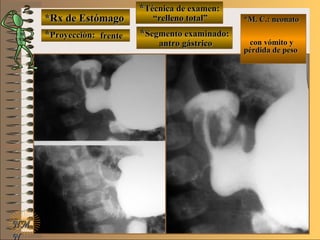

*Rx de Estómago*Rx de Estómago

**Proyección:Proyección:

**Técnica de examen:Técnica de examen:

**Segmento examinado:Segmento examinado:

*M. C.:*M. C.:

epigastralgiaepigastralgia

melenamelena

NMNM

detalledetalle

frentefrente

““doble contraste”doble contraste”

antro gástricoantro gástrico

A-A-El examen es normal o patológico?El examen es normal o patológico?

Examen patológico de estómago con técnica deExamen patológico de estómago con técnica de

doble contraste en proyección de frentedoble contraste en proyección de frente

B-B-La patología es congénita o adquirida?La patología es congénita o adquirida?

Patología adquiridaPatología adquirida

C-C- Dicha patología es orgánica, funcional o mixta?Dicha patología es orgánica, funcional o mixta?

**OpciónOpción

Patología adquirida orgánicaPatología adquirida orgánica

D-D-La misma es neoplásica o no neoplásica?La misma es neoplásica o no neoplásica?

Patología adquirida orgánica no neoplásicaPatología adquirida orgánica no neoplásica

E-E-Puede describir la o las imágenes patológicas?Puede describir la o las imágenes patológicas?

Se identifican en antro gástrico múltiplesSe identifican en antro gástrico múltiples imáge-imáge-

nes mixtasnes mixtas UNTUNT : elevado (inflamación) y: elevado (inflamación) y

deprimidas (erosión) focales compatibles condeprimidas (erosión) focales compatibles con

una gastritis madura completauna gastritis madura completa

**Opción avanzada para volver a ver las imágenes con reparosOpción avanzada para volver a ver las imágenes con reparos